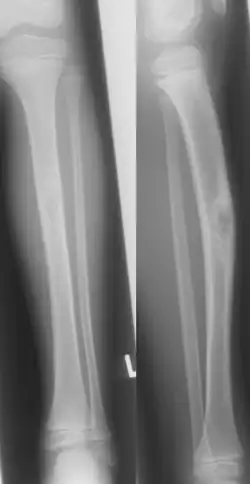

Jaffe-Campanacci-Syndrome, boy 7 Y, tibial bowing and cortical/subcortial mixed sclerosis | |

Jaffe–Campanacci syndrome is one of the disorders associated with café au lait macules (CALMs). Presentations may include intellectual disability, disseminated non-ossifying fibromas of the long bones and jaw, hypogonadism or cryptorchidism, or giant cell granulomas of the jaw.[2]